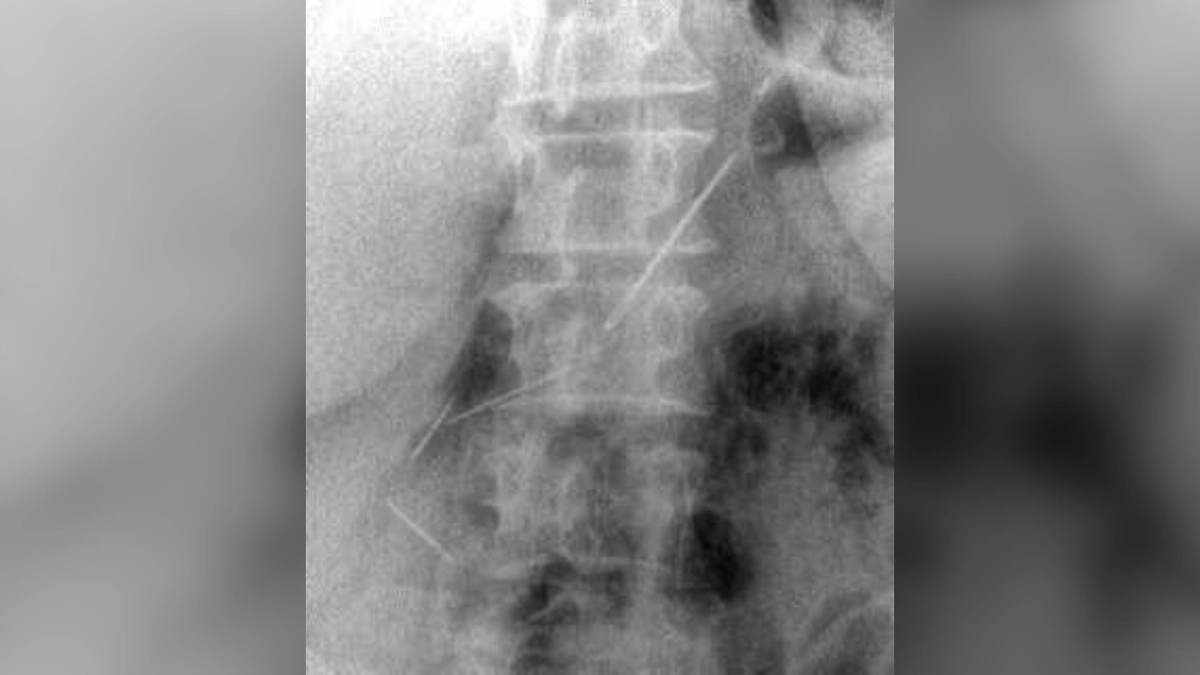

Пациентка из Красногорска полтора месяца ходила с опасным грузом в животе. Врачи достали из неё четыре швейные иглы. 59-летняя женщина обратилась в больницу с болями. Диагностика показала: три иглы в брюшной полости и одна — в передней брюшной стенке, сообщили в Минздраве Московской области.

Как выяснилось, пациентка проглотила их около месяца назад. За это время инородные предметы успели обрасти тканями. Заведующий первым хирургическим отделением Николай Мурашов рассказал, что сначала планировали лапароскопию, но из-за кровотечения пришлось делать лапаротомию с рассечением стенки. Иглы прошли через желудок, одна даже задела поджелудочную — её удалось сохранить.